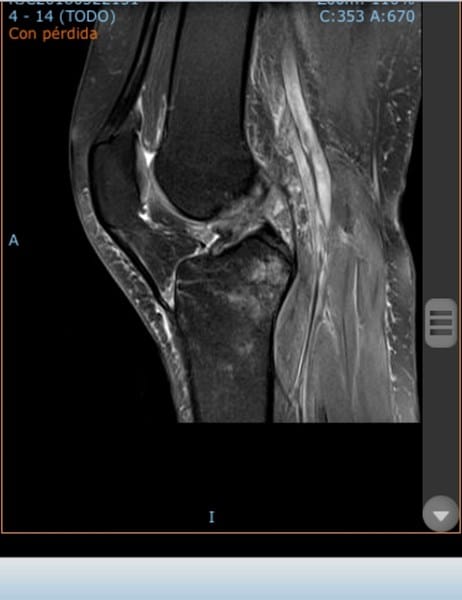

¿Es posible que tenga una Rotura de LCA o menisco?

Hace más de un mes me lesioné esquiando y todavía no sé los resultados de la resonancia, sólo he podido ver las imágenes... Tengo la rodilla bloqueada en 10-90 grados y dolor intermitente, a penas puedo caminar.. Podría ser el ligamento, ¿el menisco o ambas?